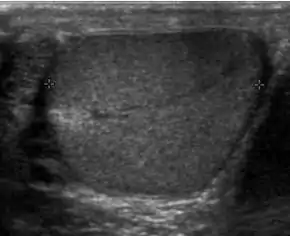

Undescended testis is found in 4% of full-term infants but only 0.8% of males at the age of 1 year have true cryptorchidism. Although an undescended testis can be found anywhere along the pathway of descent from the retroperitoneum to the scrotum, the inguinal canal is the most common site for an undescended testis. Deviation of testis from the normal pathway of descent will result in ectopic testis that is commonly seen in pubopenile, femoral triangle and perineal regions.

Besides infertility, undescended testes carry an increased risk of malignancy even for the normally located contralateral testis. The risk of malignancy is estimated to be as high as 10 times the normal individual with seminoma being the most common malignancy.

The incidence of infertility is decreased if surgical orchiopexy is carried out before the 1–3 years but the risk of malignancy does not change. Because of the superficial location of the inguinal canal in children, sonography of undescended testes should be performed with a high frequency transducer. At ultrasound, the undescended testis usually appears small, less echogenic than the contralateral normal testis and usually located in the inguinal region [Fig. 29]. With color Doppler, the vascularity of the undescended testis is poor.

Fig. 29. Undescended testis. (a) Normal testis in the scrotum. (b) Atrophic and decreased echogenicity of the contralateral testis of the same patient seen in the inguinal region.